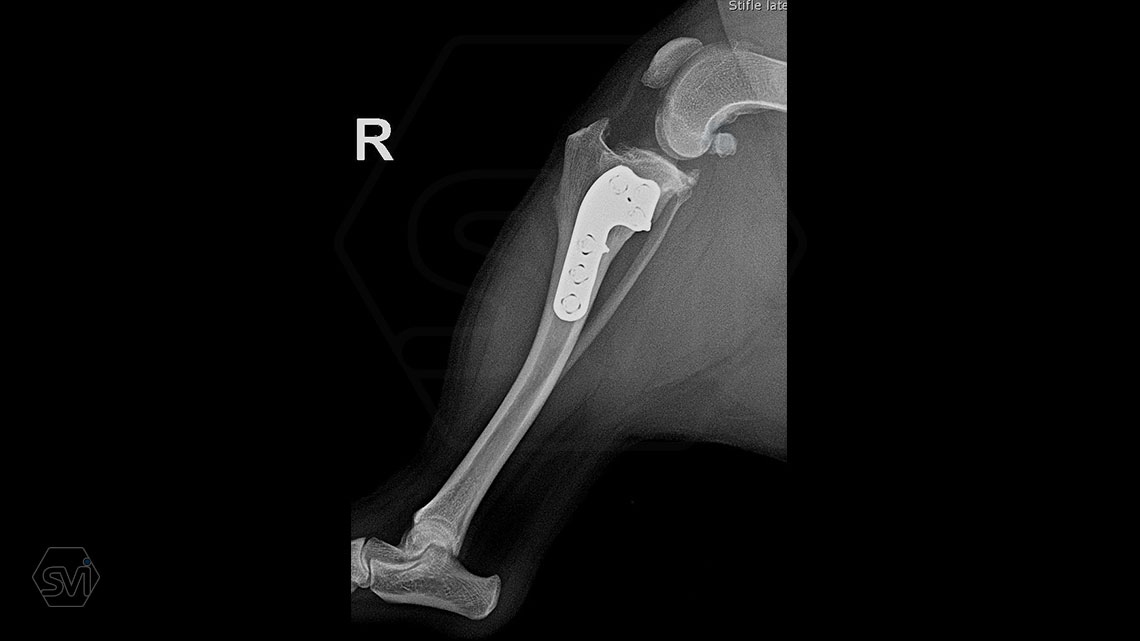

The cranial cruciate ligament rupture of a 7-year-old 8 kg active mix dog was solved a year ago with a precontured polyaxial 2.4mm system, now the other leg has been laid out, and this plate was used here as well. The stability of the system, its fit to the bone and the good healing can be measured nicely on the 1-year control X-ray.

The 2.4 system is great to use where the 2.0mm is already small, but the 2.7mm is still very big. This is a populous family of 6-14 kg dogs, according to our own data for 2021, the 2.4 mm size makes up 14% of all TPLO surgeries!